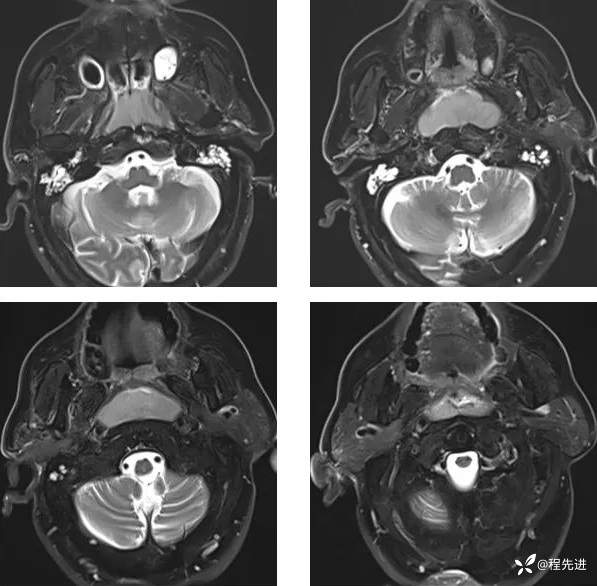

MR平扫+增强:

T2: